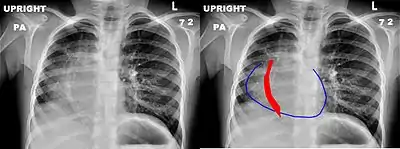

Scimitar syndrome, or congenital pulmonary venolobar syndrome, is a rare congenital heart defect characterized by anomalous venous return from the right lung (to the systemic venous drainage, rather than directly to the left atrium).[1] This anomalous pulmonary venous return can be either partial (PAPVR) or total (TAPVR). The syndrome associated with PAPVR is more commonly known as Scimitar syndrome after the curvilinear pattern created on a chest radiograph by the pulmonary veins that drain to the inferior vena cava.[2] This radiographic density often has the shape of a scimitar, a type of curved sword.[2] The syndrome was first described by Catherine Neill in 1960.[3]

The anomalous venous return forms a curved shadow on chest x-ray such that it resembles a scimitar. This is called the Scimitar Sign. Associated abnormalities include right lung hypoplasia with associated dextroposition of the heart, pulmonary artery hypoplasia and pulmonary sequestration. Incidence is around 1 per 100,000 births.[4]